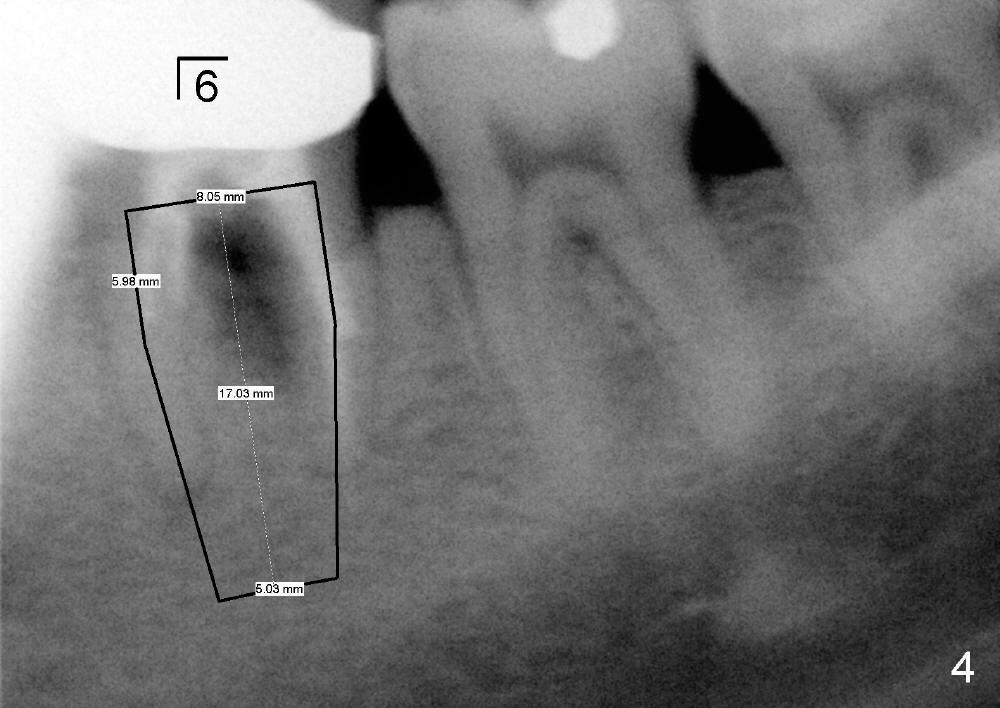

接电话同时研究他现有的X光片(图四,图形不清楚),那是五年前拍摄的,显示左下第一磨牙根分叉阴影,根管治疗不全,那颗牙齿确死无疑,同意他来诊所拔牙,即刻植牙(图四方块:植牙设计)。临时召集两位助手上班。